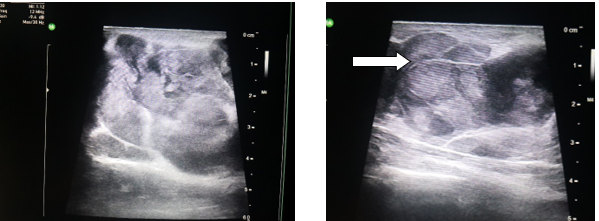

Hình 2: Siêu âm tuyến vú hai bên: Nhiều khối giảm âm tuyến vú hai bên, to hơn ở bên trái, khối lớn nhất kích thước 7,5 x 5,5cm, ranh giới rõ, bờ đa cung, trong có vách (mũi tên trắng), tăng sinh mạch trong các vách, không có vi vôi hóa, không thấy dấu hiệu xâm lấn da và cơ ngực (phân loại BIRADS -3). Không thấy hạch nghi ngờ ác tính hố nách hai bên.